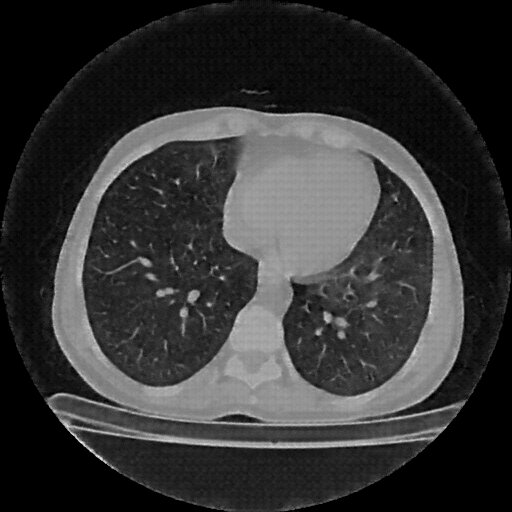

Reconstructed NATIVE CT scan (cycle consistency)

Full window (WL 1023.5, WW 4095 β†’ Low βˆ’1024, High +3071)

Lung window (WL -600, WW 1500 β†’ Low βˆ’1350, High +150)